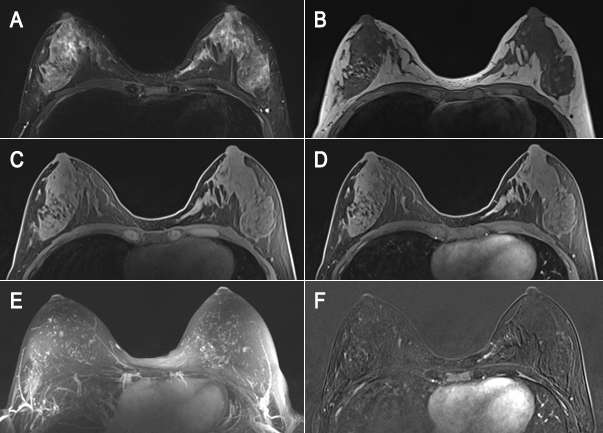

Female with recently diagnosed invasive lobular carcinoma underwent breast MRI for evaluation of extent of disease

Figure 2. 66-year-old female with recently diagnosed invasive lobular carcinoma underwent breast MRI for evaluation of extent of disease. Initially, she was seen for a palpable lump in the left breast. (A) Diagnostic mammograms in CC and MLO view demonstrated a partially visualized focal asymmetry at 3 o’clock, posterior depth in the region of the palpable abnormality. (B) Diagnostic ultrasound showed vague shadowing at 3-4 o’clock, which was biopsied and resulted as invasive lobular carcinoma. (C) T1-weighted fat saturated post contrast and (D) subtraction imaging showed a large area of non-mass enhancement in the left outer breast overall occupying 4-6 o’clock and extending to the chest wall with enhancement of the left pectoralis muscle, consistent with disease involvement. More inferiorly (not pictured) was associated retraction and focal enhancement along the inferolateral left breast.